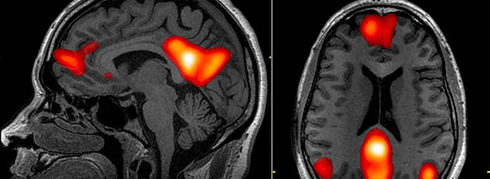

Son yıllarda yapılan fMRI (fonksiyonel manyetik rezonans görüntüleme) ve diğer beyin görüntüleme çalışmaları, kronik yalnızlık yaşayan bireylerin beyinlerinde belirgin farklılıklar olduğunu gösteriyor.

Varsayılan Mod Ağı (Default Mode Network - DMN) Aktivitesi: Yalnızlık hisseden bireylerde, beynin içe dönük düşünceler ve kendini yansıtma ile ilişkilendirilen Varsayılan Mod Ağı'nın (DMN) daha aktif olduğu gözlemleniyor. Bu durum, yalnız kişilerin geçmiş anıları düşünmeye veya geleceği hayal etmeye daha fazla zaman harcadıklarını, ancak sosyal etkileşimlere daha az odaklandıklarını gösteriyor.

Sosyal Biliş Bölgelerindeki Değişimler: Yalnızlık, beynin sosyal etkileşimleri işlemleme ve başkalarıyla empati kurma ile ilgili bölgelerinde (örneğin temporal parietal kavşak) farklılıklar yaratabilir. Bu da yalnızlık döngüsünü pekiştiren bir etkiye sahip olabilir.

Stres Yanıtı ve Amigdala: Kronik yalnızlık, beynin tehditleri işleyen ve korku yanıtını tetikleyen amigdala bölgesinin daha aktif olmasına neden olabilir. Bu durum, yalnız bireylerin sosyal durumlara karşı daha yüksek stres tepkileri vermesine ve daha kaygılı hissetmesine yol açabilir. Sürekli yüksek stres seviyeleri, kortizol gibi hormonların kronik olarak yükselmesine ve beyin sağlığını olumsuz etkilemesine neden olabilir.